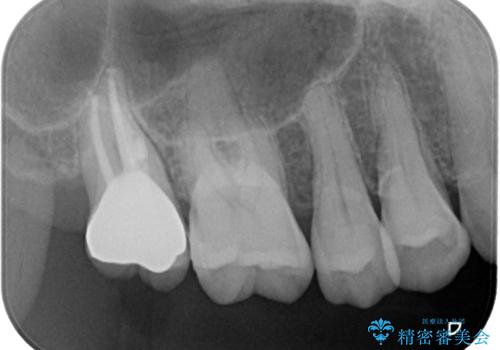

レントゲン写真などで診査を行ったところ、神経組織が壊死し、根尖部周辺の骨に炎症が認められました。

補綴後6ヶ月経過しレントゲンを撮影したところ、根尖周辺の病変が消失していることが確認できました。